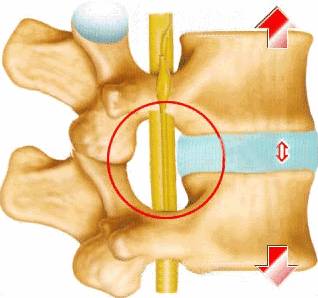

脊椎矫正原理

低头玩手机脑子竟然漏水了